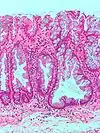

| Traditional serrated adenoma | Colorectal | Serrated crypts, often villous architecture, with cytologic atypia, eosinophilic cells | Yes | ![]() |

Serrated polyposis syndrome |